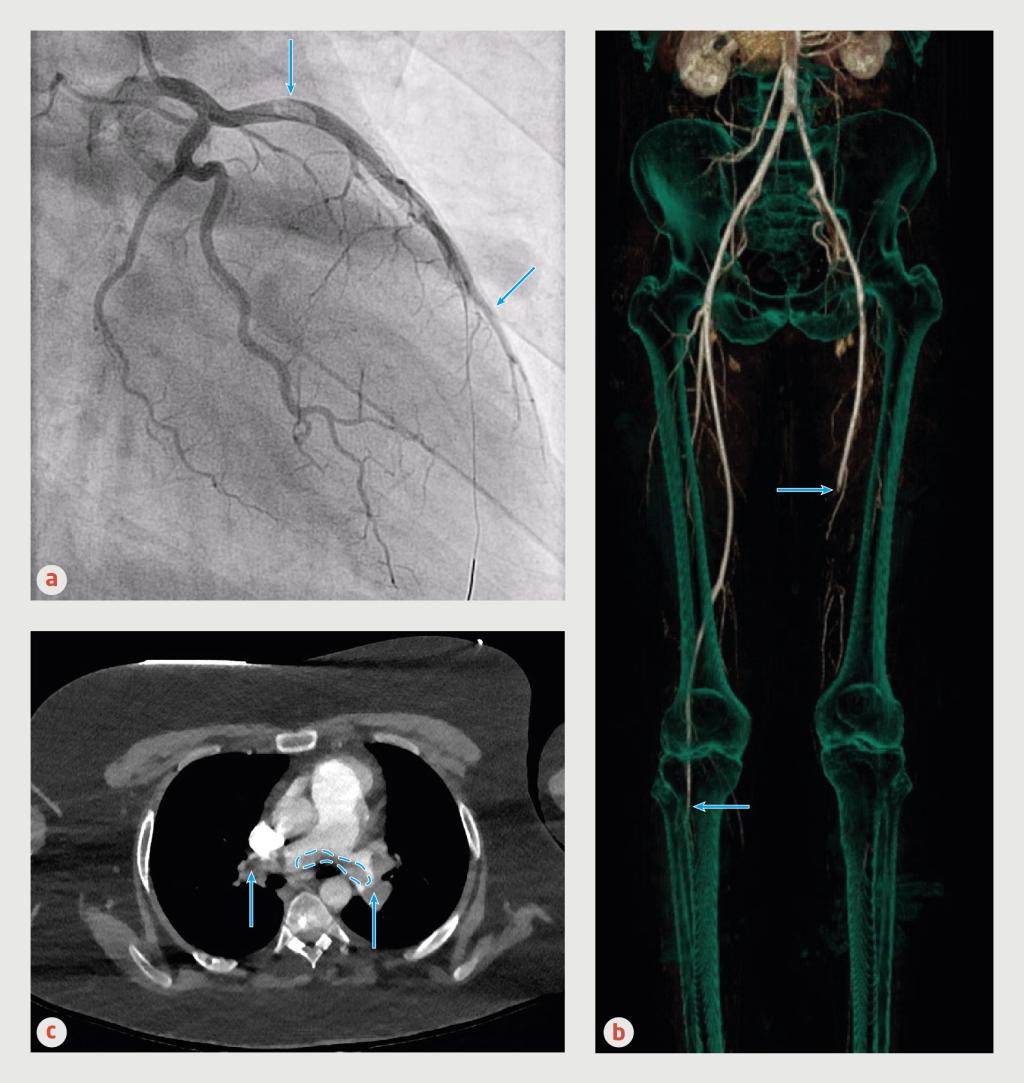

Trombo-embolieën van patiënt A, B en C

Figuur 2 | Trombo-embolieën van patiënt A, B en C

(a) Coronair angiogram van patiënt A. Proximaal in de ramus interventricularis anterior van de linker coronairarterie (‘left anterior descending artery’) is een grote trombus zichtbaar (pijl) met distaal een trombotische occlusie van deze arterie (pijl). (b) CT-angiografie van de buik-, bekken- en beenvaten van patiënt B. Aan de rechterzijde is een occlusie zichtbaar vanaf de crurale arteriën (pijl). Aan de linkerkant is de distale A. femoralis superficialis (pijl) geoccludeerd en is de A. femoralis profunda over het gehele traject dicht. In de A. femoralis superficialis en de A. iliaca communis aan linkerzijde zijn trombi zichtbaar. (c) Transversale opname van een CT-angiografie van thorax van patiënt C. Zowel in de linker als de rechter A. pulmonalis zijn obstruerende trombi aanwezig (pijlen). In de bifurcatie van de Aa. pulmonales is een trombus zichtbaar (omlijnd), passend bij een ruiterembolus.